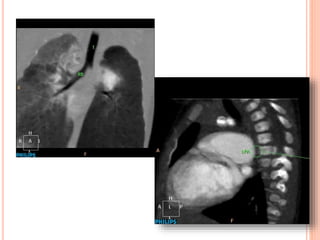

CASE #1 13MONTH-OLD BOY S/P TOF REPAIR

Huge RPA HugeMPA Severe PS Aneurysmal RVOT